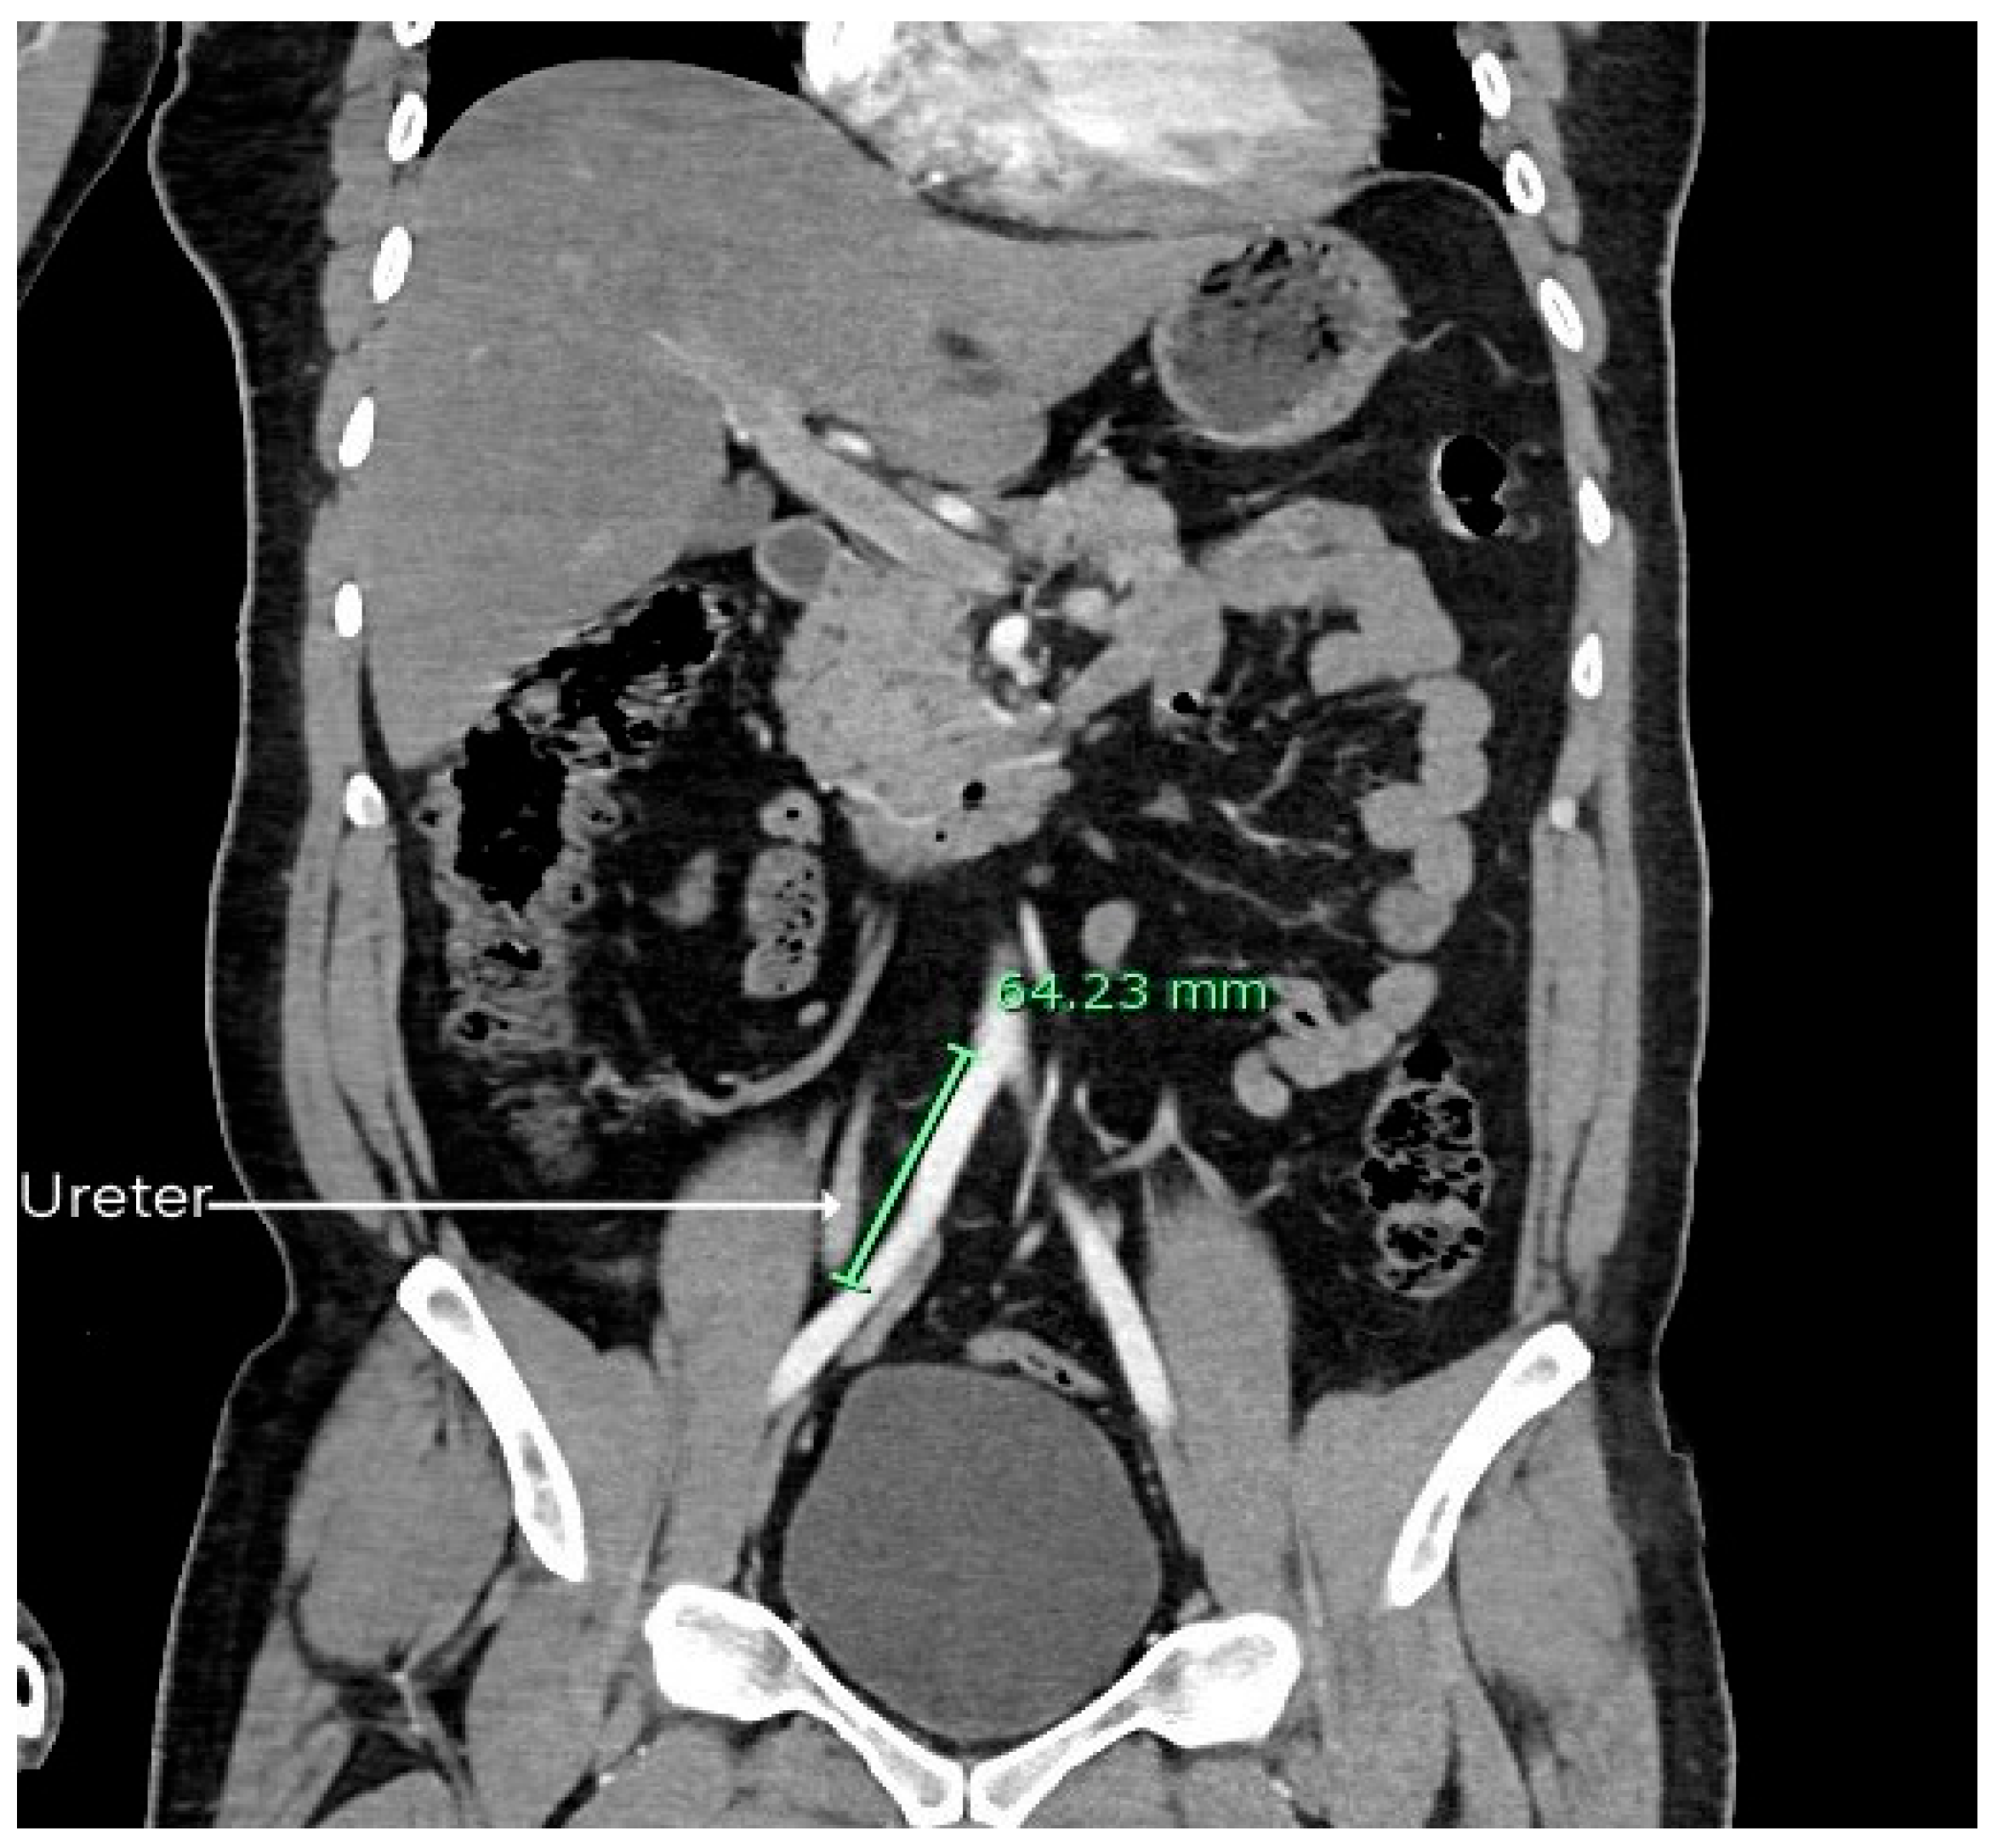

Level of Abdominal Aorta Bifurcation and Its Relation to the Ureter: A Radiological Study with Clinical Implications

3. Results